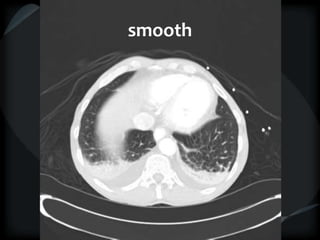

Septal Pattern – lymphatic/venous

● Smooth – pulmonary veno-occlusive disease, mitral

stenosis, capillary hemangiomatosis, LC

smooth

LC

beaded

Septal Pattern –lymphatic/venous  Secondary lobule outlined- interlobular septum ● Smooth – pulmonary veno-occlusive disease, mitral stenosis, capillary hemangiomatosis, LC ● Beaded – lymphangitic carcinomatosis, lymphoma, lymphangiomatosis, sarcoid Rare = non-Langerhans’ cell histiocytosis (bone+pleura) amyloidosis